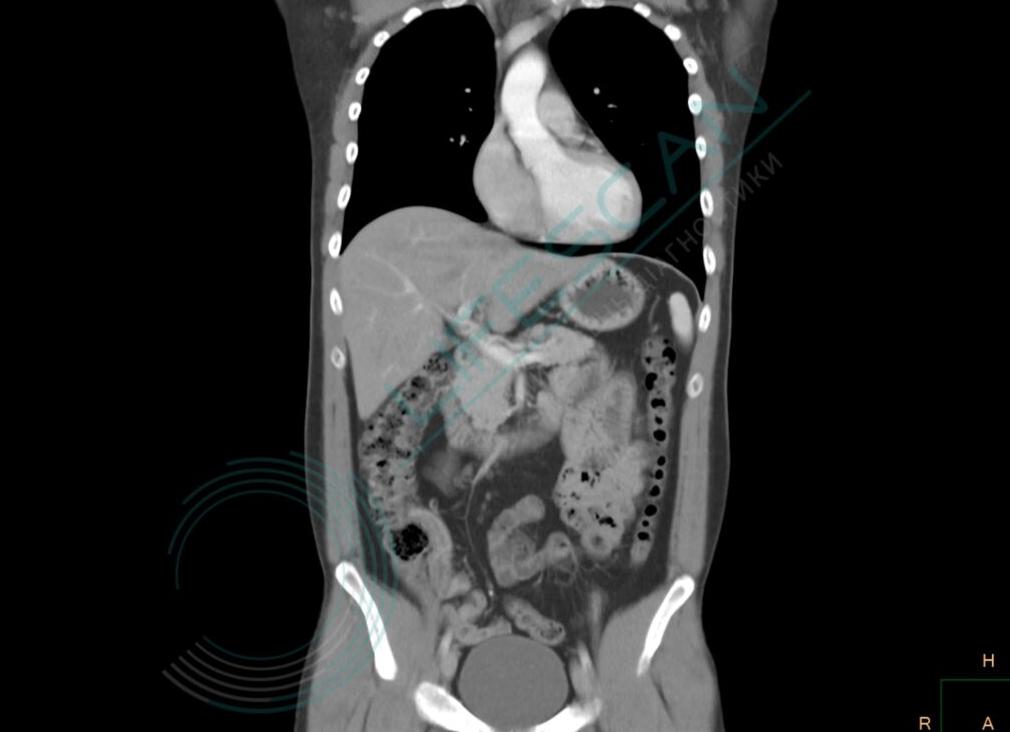

Магнитно-резонансная и компьютерная томография — высокотехнологические исследования, благодаря которым можно выяснить причину болей в пояснице, отеков, обнаружить болезнь почек, когда она еще никак не проявляется. Пациентам важно понимать, что лучше — КТ или МРТ почек, и на чем основывается врач, когда назначает тот или иной метод исследования.